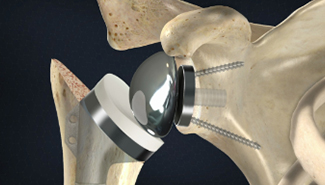

Total Hip Arthroplasty

Ran Schwarzkopf, MD, MSc

Topics include: implant design features including tribology, conversion total hip arthroplasty, acetabular bone loss, femoral reconstruction and periprosthetic fractures.

50 CME Credits

6 Modules, 25 Lessons